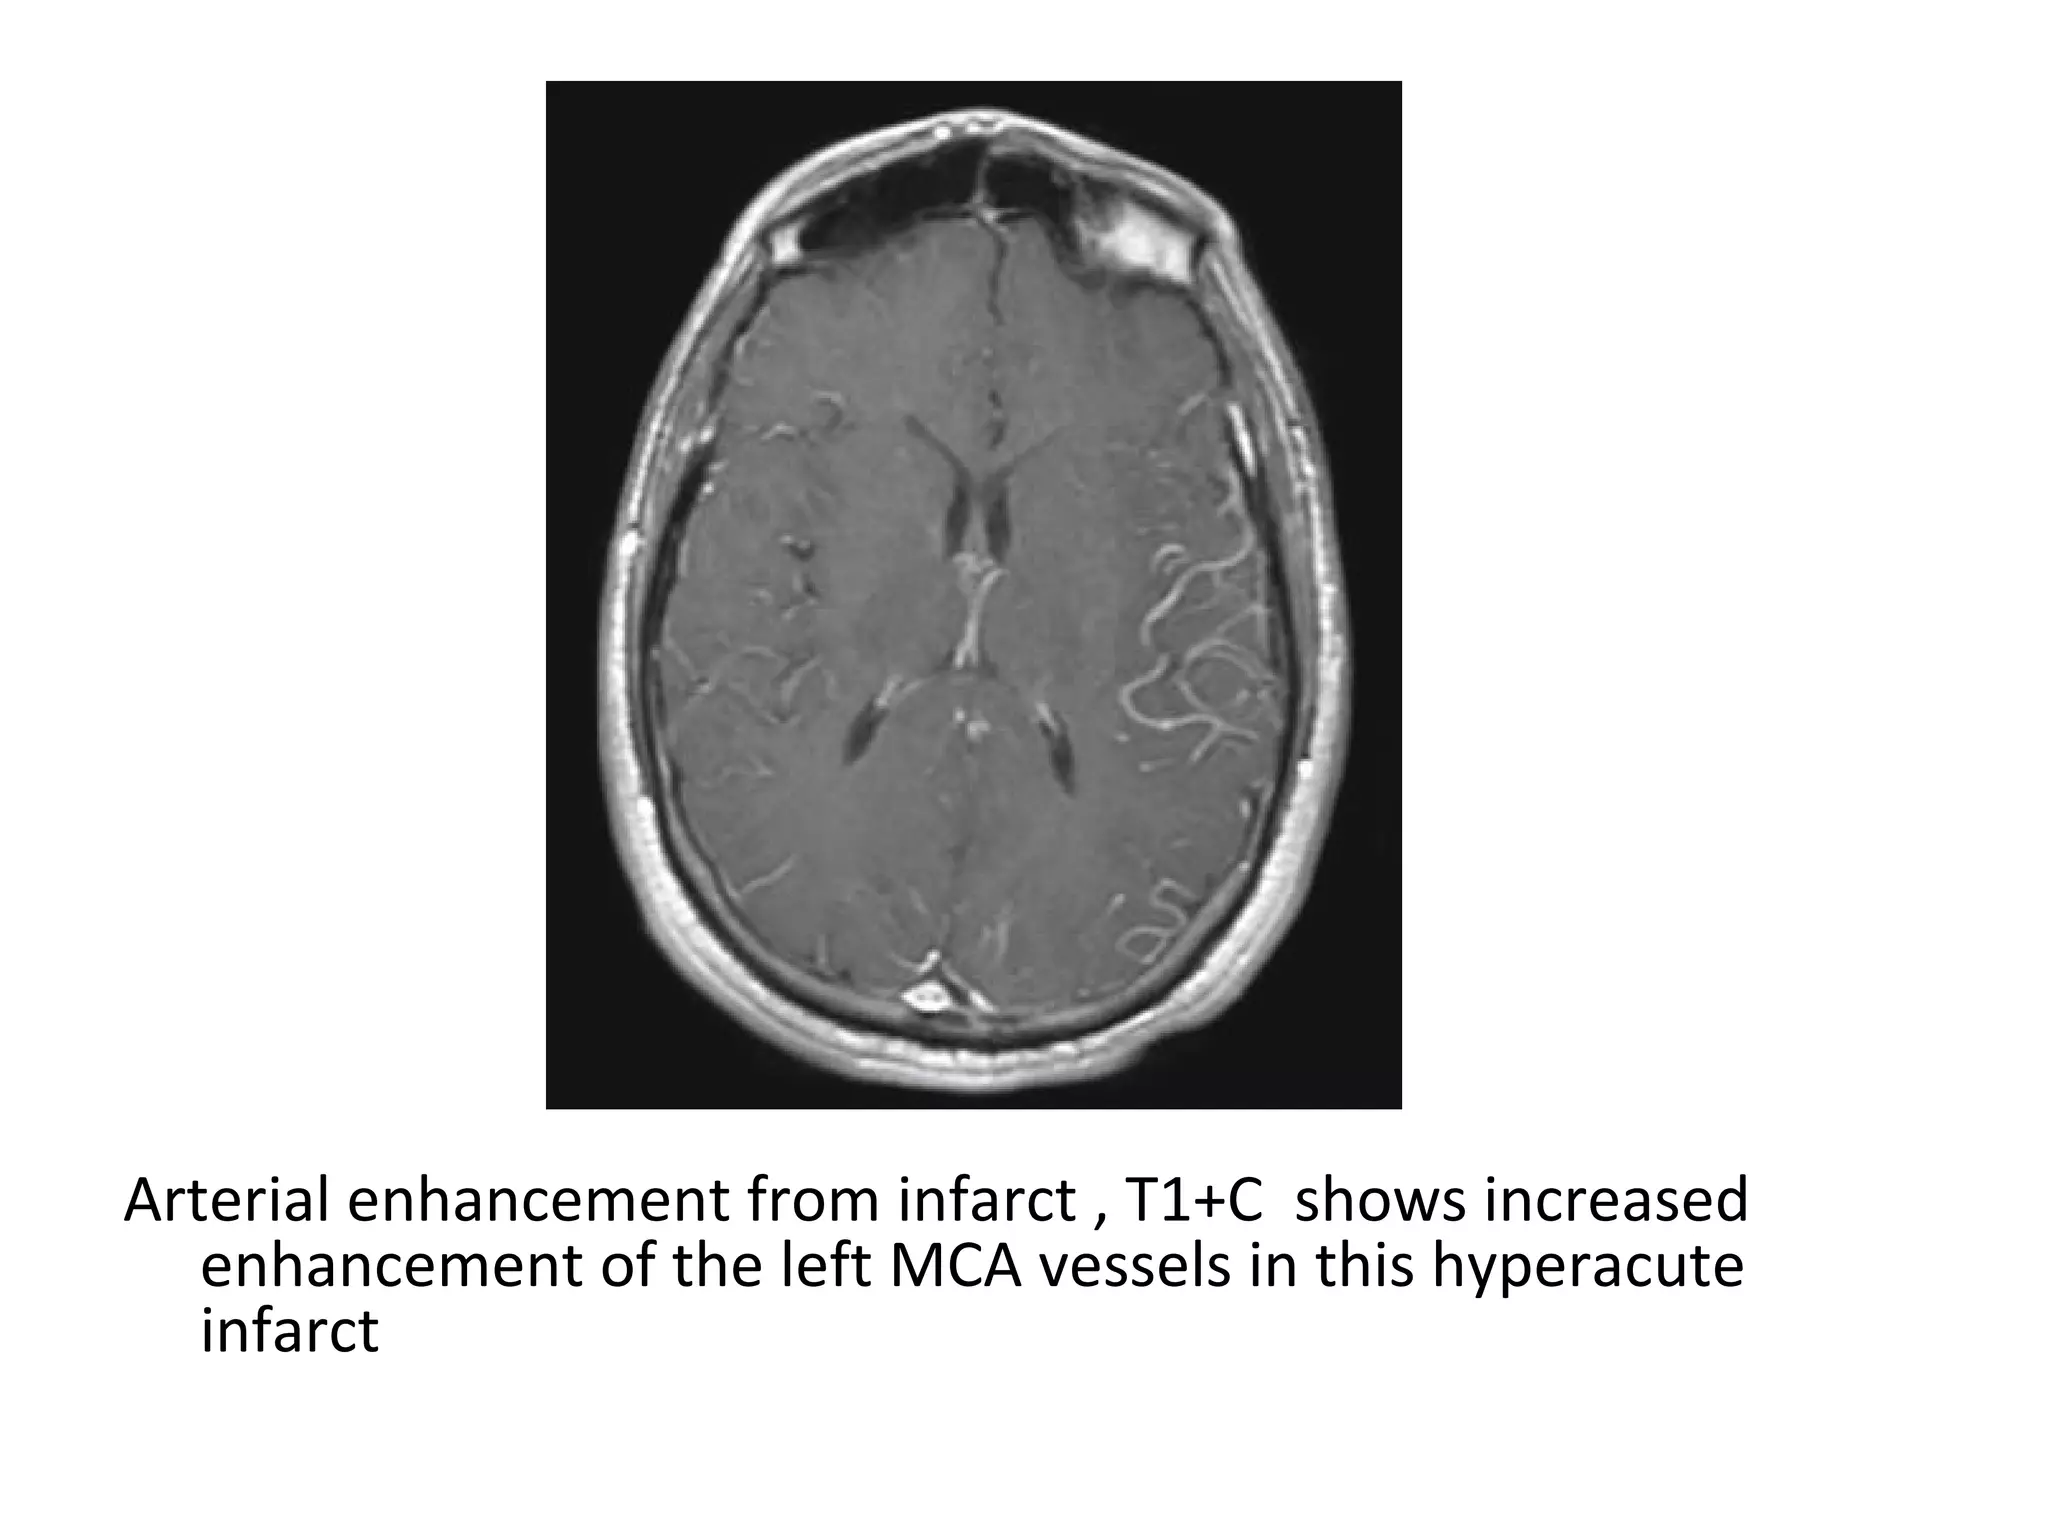

5-Intravascular Stasis of Contrast Medium :

-Prolonged transit of contrast medium through

distal / collateral vessels causes high arterial

signal on post-gadolinium T1W images

Arterial enhancement from infarct , T1+C shows increased

enhancement of the left MCA vessels in this hyperacute

infarct

4 hrs after left MCA symptoms began , extensive Intravascular

enhancement seen (an immediate finding)